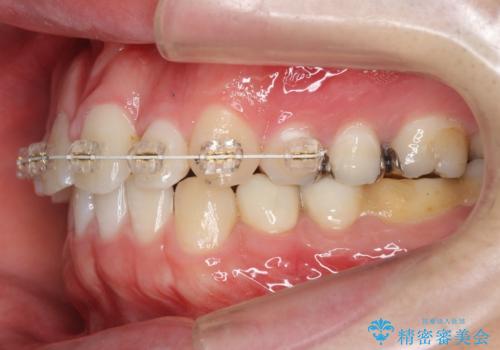

前歯のねじれ 上だけ部分矯正でコストダウン

- 前歯のねじれを部分矯正で治療しました。

奥歯のかみ合わせを変えずに、費用を抑えて短期間に治療したい方におすすめです。

奥歯のかみあわせも問題なく、また、下の前歯のがたつきが元からない場合は上の部分矯正が十分可能です。

上下親知らずの抜歯や虫歯処置も矯正前後で行っています。